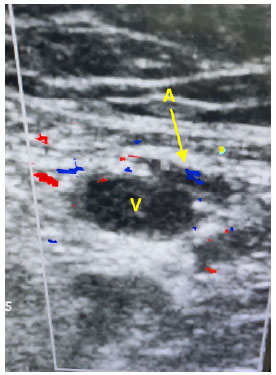

Com auxílio de aparelho de Ultrassonografia portátil, decidi por fazer uma varredura nos principais vasos cervicais e de membros inferiores, pois havia necessidade de troca de cateter para prosseguir com as sessões de hemodiálise da paciente. No caso da paciente, havia o relato de dificuldade de punções anteriores, além de dor e edema em membro inferior direito e sangramento no orifício de punção associado a baixo fluxo no cateter da veia jugular interna esquerda. Inicialmente, avaliei os vasos inguinofemorais da paciente. À esquerda, em todo o trajeto para possíveis punções, a artéria estava por cima da veia, o que dificultaria sua punção “às cegas”. Veias femorais comum e superficial e veia poplítea esquerdas apresentavam bom fluxo ao doppler em cores e com boa compressibilidade, não denotando sinais de trombos na região. Ao avaliar os vasos inguinofemorais à direita, local de tentativas prévias de punção vascular, foi evidenciado que o lúmen venoso apresentava conteúdo heterogêneo, hiperecoico, além de fluxo prejudicado visualizado no doppler em cores, denotando sinais de trombose venosa naquele sítio.